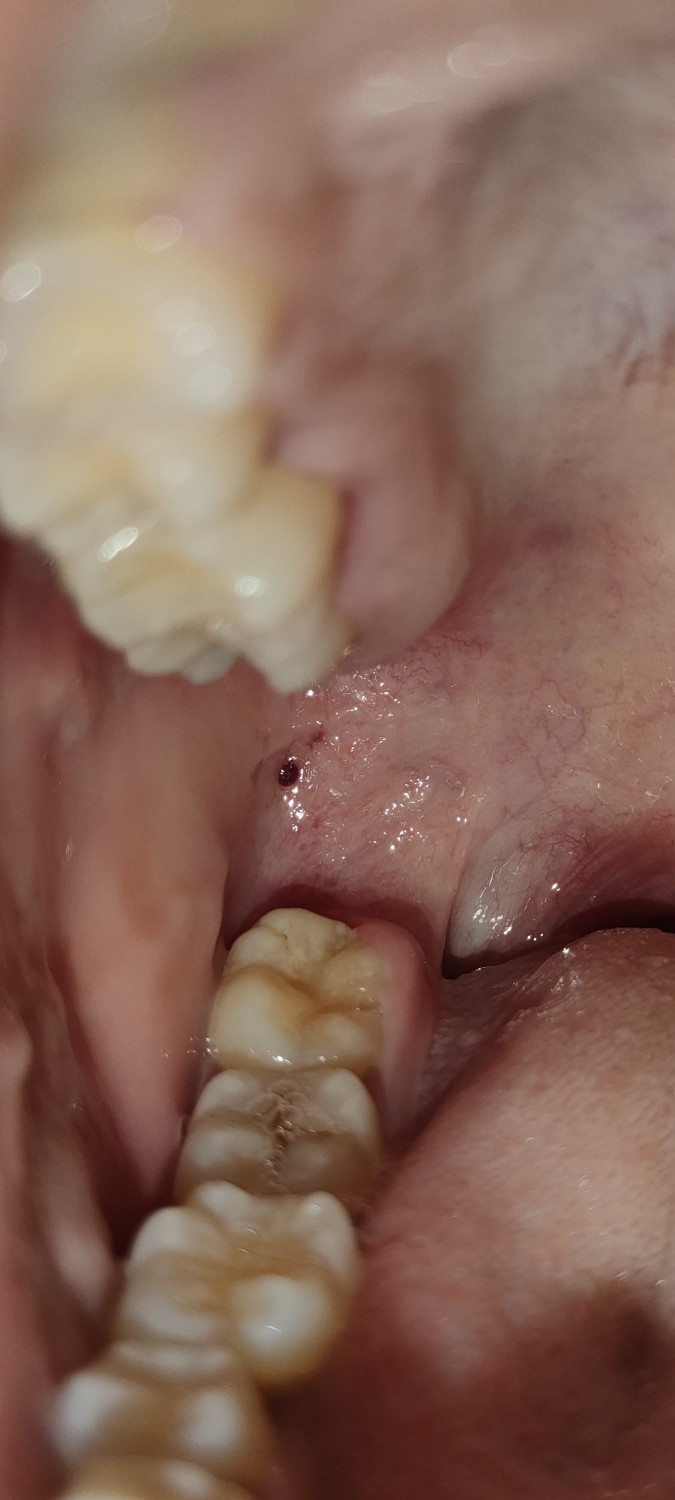

มีจุดดำๆในช่องปากอันตรายมั้ยคะ ส่วนตัวไม่ได้จัดฟันค่ะ (มีรูป) นานมั้ยคะกว่าจะหายกลัวเป็นอะไรร้ายแรงค่ะ

ตามหัวข้อเลยค่ะ มีเม็ดสีดำๆในปากเท่าที่ลองค้นหาดูน่าจะเรียกว่าห้อเลือกค่ะ คือเราไม่ได้จัดฟันนะคะแต่มีนิสัยชอบกัดเนื้อที่กระพุ้งแก้ม คือมีวิธีการรักษาอย่างไรคะ ห